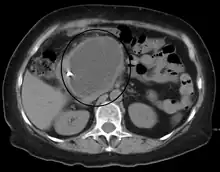

A pancreatic pseudocyst as seen on CT

A pancreatic pseudocyst is a circumscribed collection of fluid rich in pancreatic enzymes, blood, and non-necrotic tissue, typically located in the lesser sac of the abdomen. Pancreatic pseudocysts are usually complications of pancreatitis,[5] although in children they frequently occur following abdominal trauma. Pancreatic pseudocysts account for approximately 75% of all pancreatic masses.[6]

CT scan

• Computerized tomography[10] – this is the gold standard for initial assessment and follow-up.